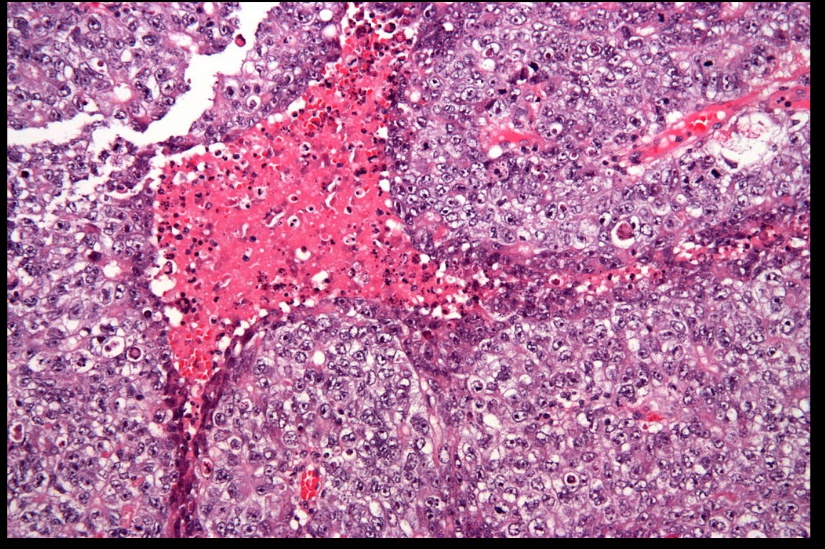

Embryonal Carcinoma

_Rare malignant tumor comprised of immature, primitive cells that form papillary/glandular structures. Metastasis is commonly hematogenous.,

_On histology will appear as sheets of undifferentiated cells with marked nuclear atypia, prominent nucleoli, and focal glandular differentiation or papillary morphology.,

Neoplastic cells displaying nuclear atypia, prominent nucleoli, and necrosis.

Gross appearance is a pale grey, bulky, hemorrhagic and necrotic tumor.

_Are less radiosensitive than seminomas, and also more aggressive with an intermediate prognosis. Chemotherapy may result in differentiation into another type of germ cell tumor (e.g. teratoma).,